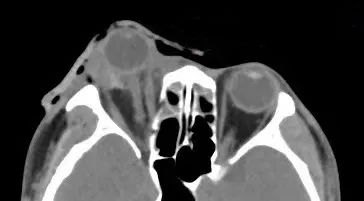

据厦门眼科中心眼外伤及眼底病二科副主任医师吴东海回忆,接诊时,陈先生的右眼眼球脱出眼眶,肿胀充血,眼睛无法正常闭合。他的视力几乎丧失,眼球上下方都有大面积的结膜裂伤。辅助检查的影像学结果显示,陈先生的伤眼近一半已脱出眼眶,眼球壁上还有星星点点的异物存留。

眼球脱出的医学影像示例。图源:宁波市医疗中心李惠利医院

所幸陈先生视神经、眼外肌肉未发生断裂,眼球壁也未破裂,但他的状况依然危急。由于眼球脱出眶外,眼睑无法正常闭合,导致角膜长时间暴露于空气中,发生了暴露性角膜炎。一旦角膜干燥感染溃疡,他将面临失明的风险。